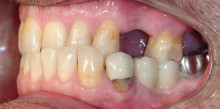

Dass nicht nur Schmelz, sondern auch häufig zahnärztliche Restaurationen einer harmonischen Zahnreihe im Wege stehen, ist leider nicht allzu selten....

Dass nicht nur Schmelz, sondern auch häufig zahnärztliche Restaurationen einer harmonischen...